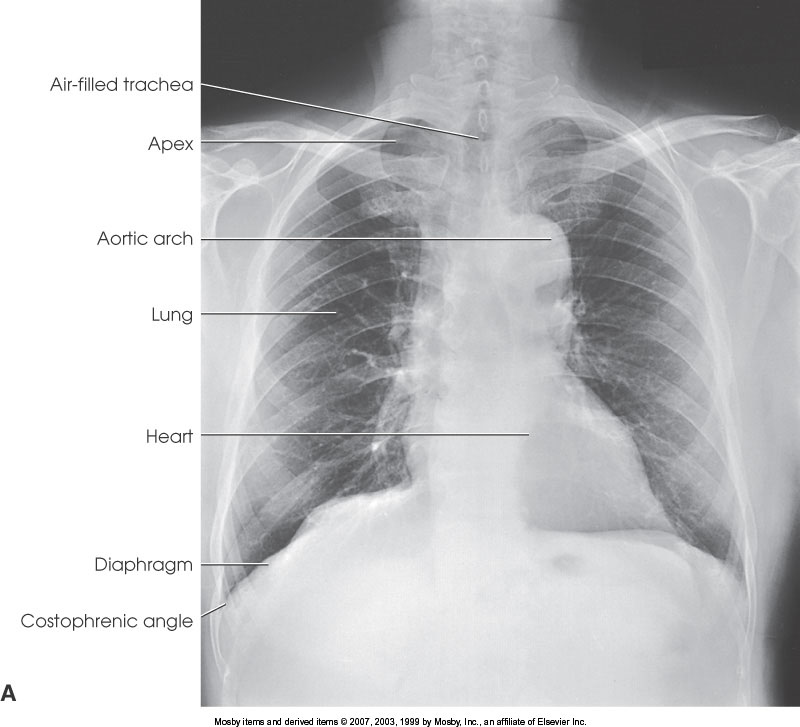

What position is demonstrated?

PA Chest